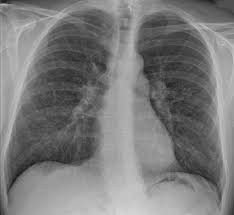

The decrease in other more severe symptoms is wheezing which if. Sarcoidosis is often identified as swollen hilar lymph nodes found in chest radiography during routine physical checkups. Sarcoidosis is a somewhat common pulmonary disease, but the concurrence of lung cancer and sarcoidosis in the same patient is very rare. Read about sarcoidosis, a chronic lung disease. By magdalena kegel | august 12, 2016.

Sarcoidosis is a chronic inflammatory condition that may increase the risk of cancer, but limited information is available on occurrence of cancer in results were generally consistent among ethnic groups, although the increased risk of colon and kidney cancer was observed only in white patients. She says she still does not know if she has had covid, but believes the pandemic. Managing sarcoidosis involves monitoring your symptoms closely to track the effectiveness of treatments. Board certification in internal medicine. The disease is referred to as systemic lesions. Read about sarcoidosis, a chronic lung disease. Sarcoidosis is a multisystem granulomatous disorder of unknown etiology that affects individuals worldwide and is characterized pathologically by the presence of noncaseating granulomas in involved organs. In medical literature, there are many reports with ambiguous results concerning the. Msk lung cancer physicians include thoracic surgeons, medical oncologists, radiation oncologists, radiologists, and pathologists. Because sarcoidosis can escape diagnosis or be mistaken for several other diseases, we can only guess at how many people are affected. Sarcoidosis is often identified as swollen hilar lymph nodes found in chest radiography during routine physical checkups. Sarcoidosis most often affects the lungs and may cause lung problems, such as: Sarcoidosis is currently thought to be associated with an abnormal immune response.